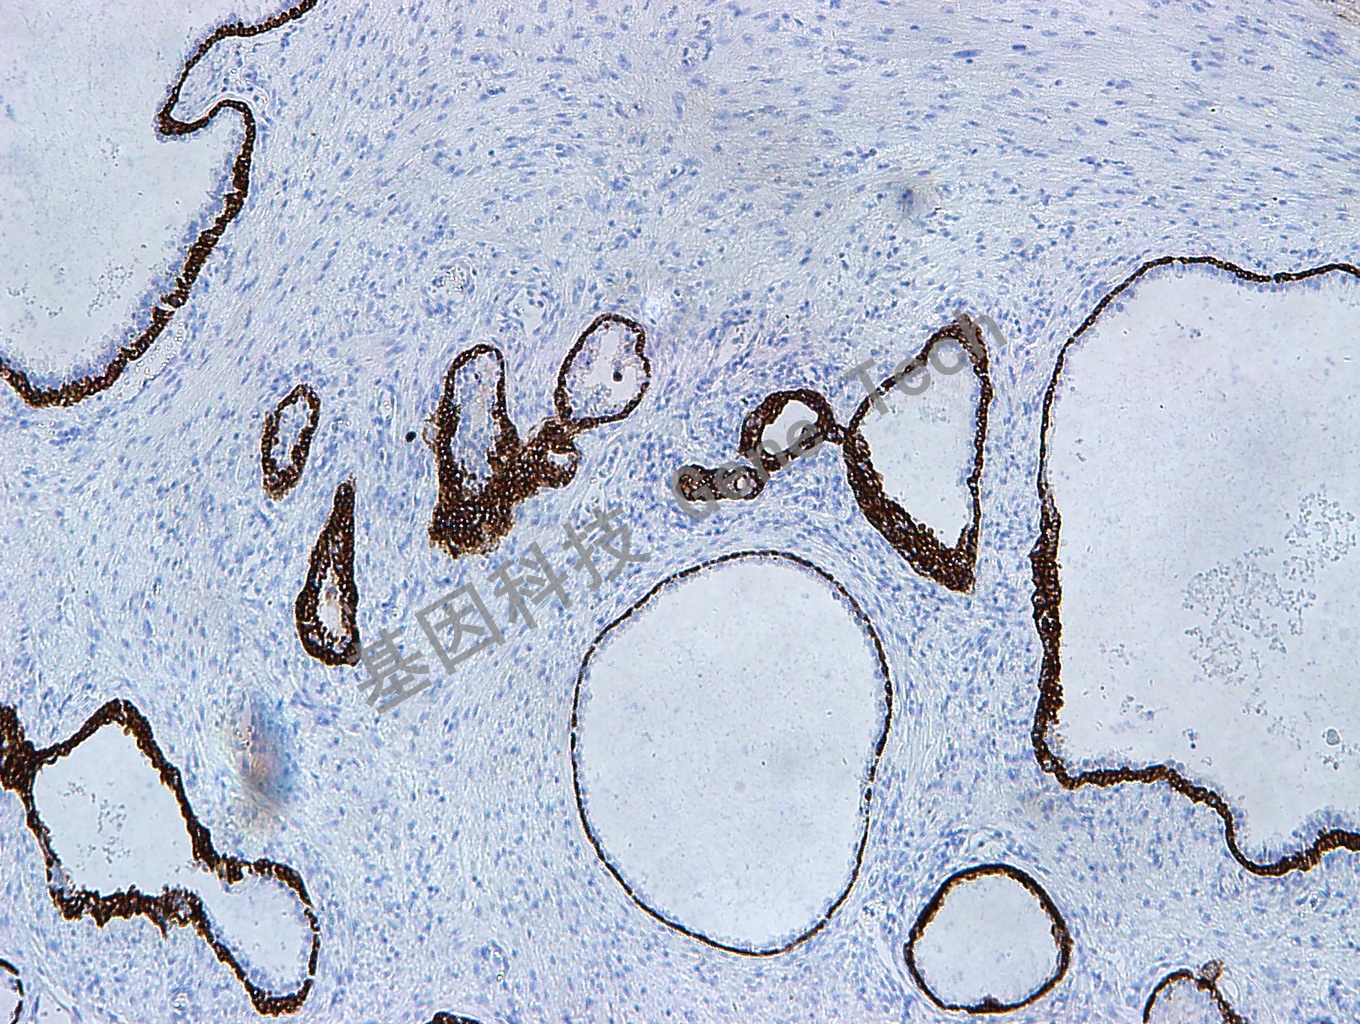

前列腺增生石蜡切片,用 CK,HMW(GM0630)染色,细胞浆阳性,DAB 显色。(10×)